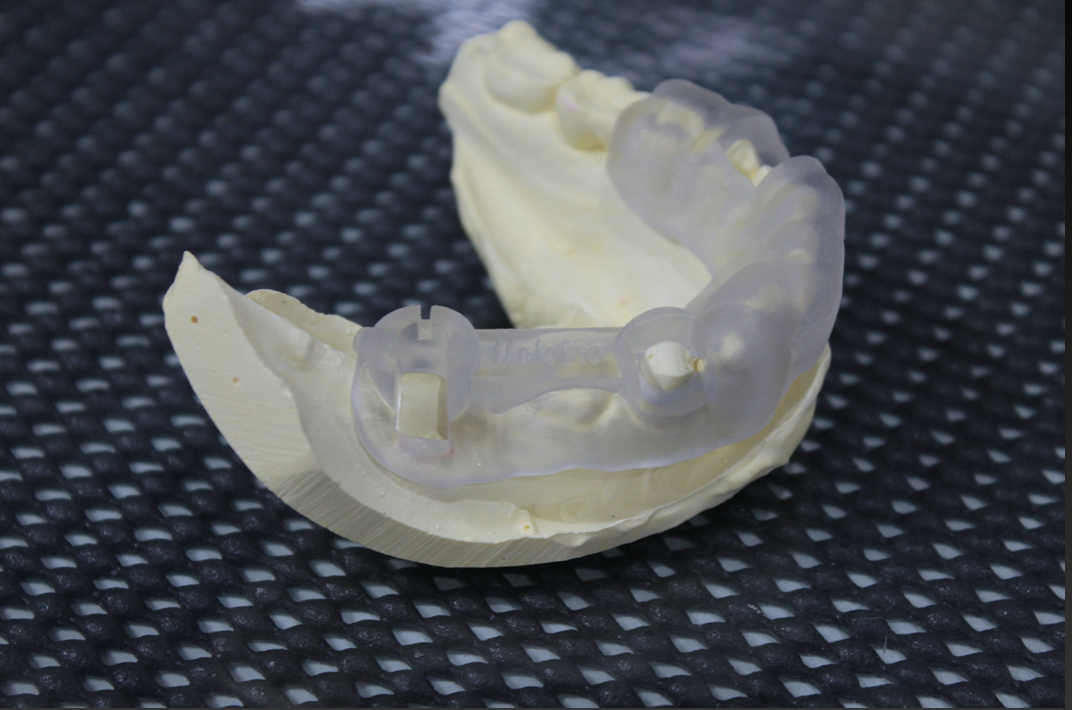

この症例は2本のインプラントを並行に入れなければならない為、オーダーメイドの手術用インプラントガイドを準備しました。

手術前に一度来院して頂いてフィットするかの確認をします。